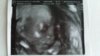

20180222_100853.jpg Hei taas pitkästä aikaa! Ajattelin tuoda lisää toivon tuulia, sillä täällä mennään jo 24. raskausviikolla ja tyttölupaus saatu :) Ultrakuva on viikolta 20 ja ensi maanantaina seuraava ultra. En meinaa vieläkään uskoa tätä todeksi, mutta on se vaan niin, kun tunnen jo 3 vkoa selvästi vauvan liikkeetkin. Hän on jo n.30cm pitkä ja painaa n.500g. <3

Mä niiiin toivon että mahdollisimman monet teistä saisitte kokea tämän saman, kaikkine puolineen. Kun se mahdollisesti tuleva palkinto on kuitenkin todella kaiken odotuksen, tuskan ja kivun arvoista. Pidän edelleen peukkuja teille jokaiselle ja onnittelut kaikille plussanneille! <3 Toivosta ei pidä koskaan luopua! <3 Voimia!